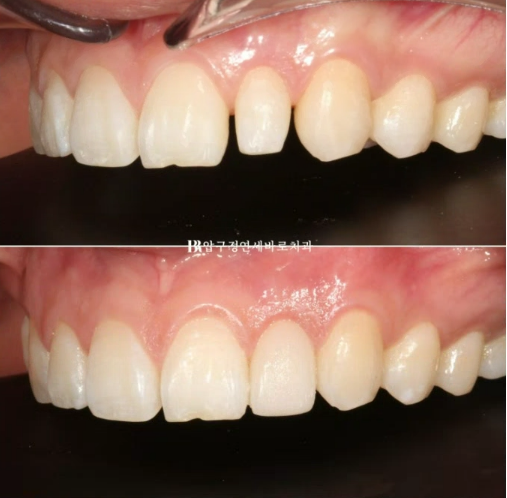

24.05

치료 마무리 단계의 사진입니다.

위 8개 아래 8개 앞니에만 장치를 붙여서 부분교정 진행중입니다.

왜소치에 라미네이트가 들어갈 공간 확보를 위해 스프링이 들어가있습니다.

7개월 후 교정이 마무리가 되었으며 왜소치 근처에 라미네이트가 들어갈 공간이 마련되어 있습니다.

이 공간을 이용해서 무삭제 라미네이트 라미네이트 젤라미까지 완료한 모습입니다.

반대쪽 치아와 같은 사이즈와 모양으로 왜소치가 회복이 되었습니다.

23.10~24.05

파란 화살표 왜소치는 정상크기로 치료가 되었습니다.

삐뚤한 앞니도 가지런해졌습니다.

교합이 떠 있던 작은어금니도 제자리를 찾았습니다.

앞니가 깊게 물리는 과개교합도 어느정도 해결이 되었습니다.

중심선 개선도 눈에 띕니다.

앞니 교정으로 이 많은 것들이 좋아졌습니다.

미소는 자연스럽게 개선이 됩니다.